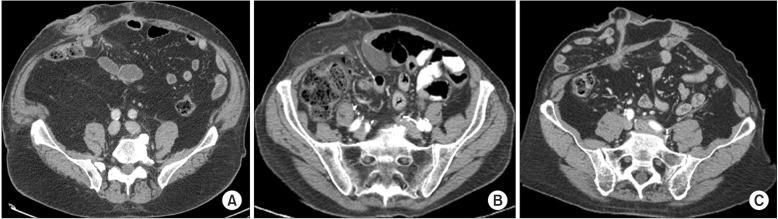

Parastomal hernia, defined as an "incisional hernia related to an abdominal wall stoma", is a frequent complication after conduit urinary diversion that can negatively impact quality of life and present a clinically significant problem for many patients. Parastomal hernia (PH) rates may be as high as 65% and while many patients are asymptomatic, in some series up to 30% of patients require surgical intervention due to pain, leakage, ostomy appliance problems, urinary obstruction, and rarely bowel obstruction or strangulation. Local tissue repair, stoma relocation, and mesh repairs have been performed to correct PH, however, long-term results have been disappointing with recurrence rates of 30%-76% reported after these techniques. Due to high recurrence rates and the potential morbidity of PH repair, efforts have been made to prevent PH development at the time of the initial surgery. Randomized trials of circumstomal prophylactic mesh placement at the time of colostomy and ileostomy stoma formation have shown significant reductions in PH rates with acceptably low complication profiles. We have placed prophylactic mesh at the time of ileal conduit creation in patients at high risk for PH development and found it to be safe and effective in reducing the PH rates over the short-term. In this review, we describe the clinical and radiographic definitions of PH, the clinical impact and risk factors associated with its development, and the use of prophylactic mesh placement for patients undergoing ileal conduit urinary diversion with the intent of reducing PH rates.

肠造口旁疝,定义为“与腹壁造口相关的切口疝”,是肠管尿流改道后常见的并发症,可降低生活质量,并给许多患者带来严重的临床问题。肠造口旁疝(PH)的发生率可能高达 65%,虽然许多患者无症状,但在一些研究中,高达 30%的患者因疼痛、渗漏、造口器具问题、尿路梗阻,且罕见的肠梗阻或绞窄而需要手术干预。局部组织修复、造口移位和网片修复已用于纠正 PH,但这些技术的长期结果令人失望,复发率为 30%-76%。由于 PH 修复的高复发率和潜在的发病率,人们已努力在初次手术时预防 PH 的发生。预防性环绕造口网片放置术在结肠造口术和回肠造口术时的随机试验显示,PH 发生率显著降低,且并发症发生率可接受。我们对有发生 PH 高风险的患者在进行回肠通道造口术时预防性放置了网片,发现其在短期内安全且有效降低 PH 发生率。在这篇综述中,我们描述了 PH 的临床和影像学定义、其发生的临床影响和危险因素,以及预防性使用网片放置术来降低接受回肠通道尿流改道术患者的 PH 发生率。